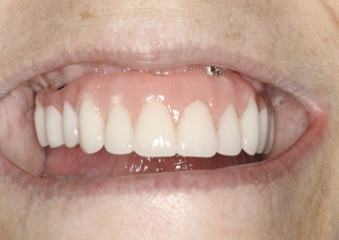

As an alternative to the relatively expensive traditional hybrid restoration that the senior population may perceive as unattainable at their age, an immediate-load all-resin provisional may often be a reasonable option as an entry-level prosthesis. This can serve for extended periods or indefinitely, and when made with a sufficient volume of resin and opposing a light occlusion such as a maxillary denture, it can offer the benefit of fixed retention at a significant reduction in expense (Figure 15 and Figure 16). Technology involving a guided approach for placing three implants universally in the same sites with pre-manufactured, one-size-fits-all bar components in the mandible can now allow placement of a final restoration in one day, again at a significantly reduced cost (Figure 17 and Figure 18).24-26 Both of these fixed options—the resin long-term provisional and the three-implant bridge—are economically comparable to the most commonly considered implant prosthesis for elderly patients, the two-implant overdenture. In contrast to the latter, however, both fixed restorations offer significant advantages in bite force, bone preservation, maintenance, and patient satisfaction that are simply unachievable with the removable implant overdenture prosthesis.27-31

Fig 15. This all-resin interim restoration, which served as a fixed long-term provisional for more than 5 years, is an example of an entry-level option that offers the physiologic benefits of a long-term fixed restoration but with an economic equivalence to a mandibular two-implant overdenture.

Figure 15

Fig 16. This all-resin interim restoration, which served as a fixed long-term provisional for more than 5 years, is an example of an entry-level option that offers the physiologic benefits of a long-term fixed restoration but with an economic equivalence to a mandibular two-implant overdenture.

Figure 16